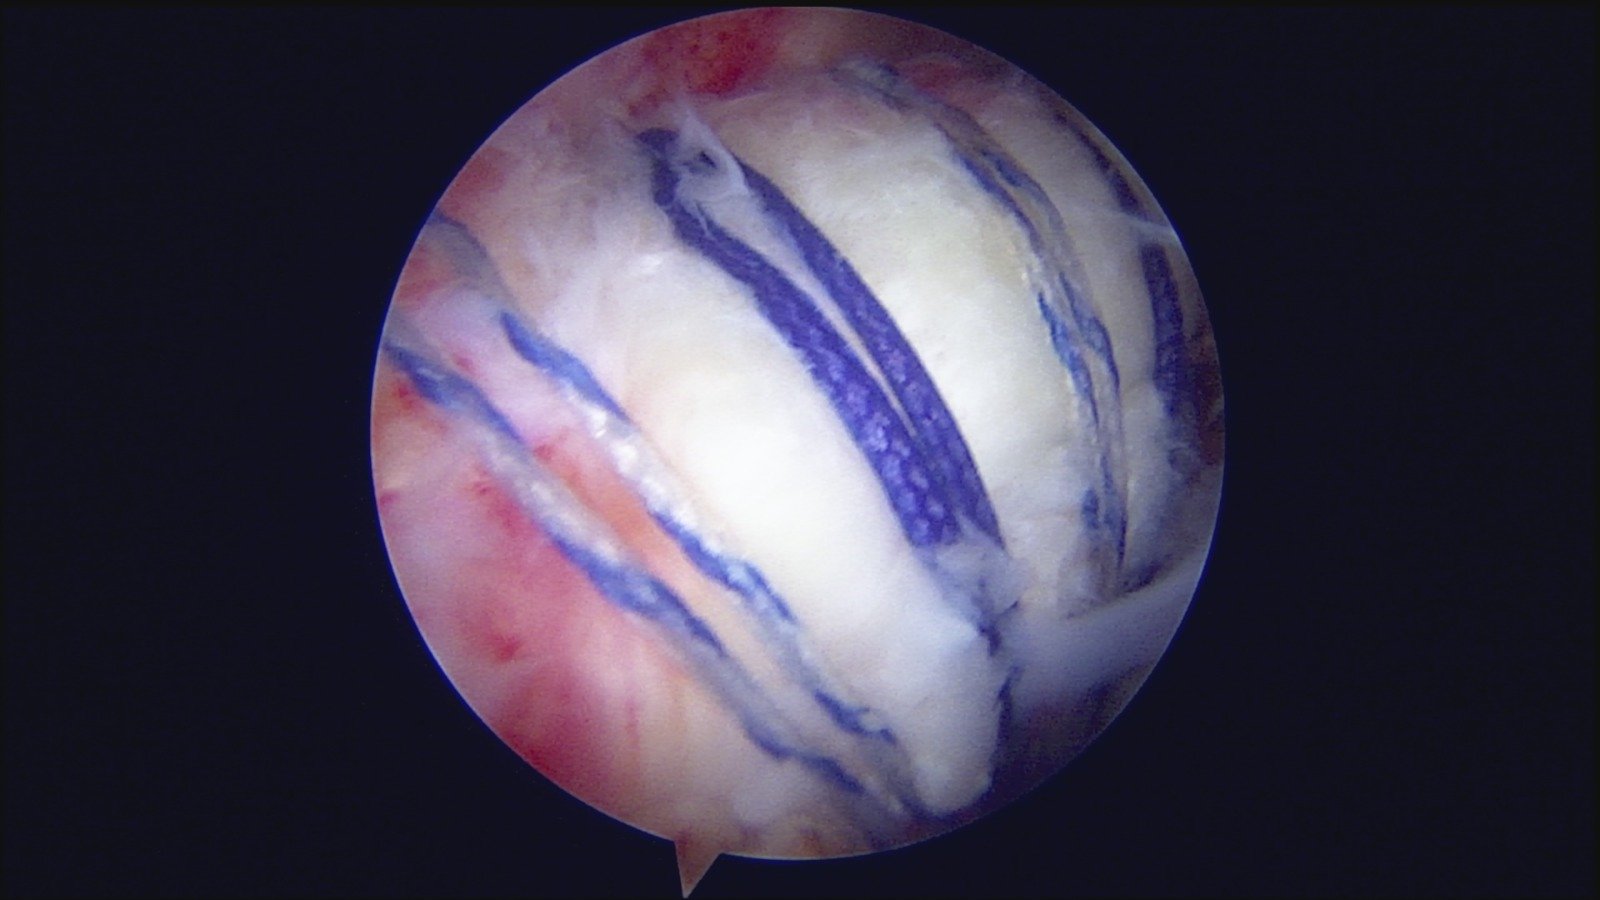

GalleryShoulder rotator cuff repair Meniscus root repair Meniscus repair Bankart repair for recurrent shoulder dislocation ACL reconstruction Machines Instruments